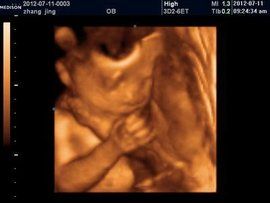

1、重度腦室增寬:(腦室寬度≥15 mm,也可稱為腦積水)指的是腦脊液過多積聚於腦室系統中,側腦室系統擴張,壓力升高,超聲檢查時表現為腦室增寬。一般側腦室三角區增寬達1.5厘米認為腦室擴大,且越寬程度越重。如果三角區寬1.2~1.4厘米,脈絡叢占滿腦室內大於50%時,一般認為正常。如脈絡叢縮小並呈懸掛狀態時,則認為有腦積水存在。

2、輕度側腦室增寬:定義為側腦室直徑≥10mm, 而≤15mm。而側腦室直徑<10mm被認為屬正常生理範圍。

側腦室增寬3、孤立性輕度側腦室增寬:是指產前系統超聲檢查無其他異常發現的病例。約10%的孤立性輕度側腦室增寬的胎兒為染色體異常,其中最多見的為21三體,孕期病毒感染特別是巨細胞病毒感染晚孕時也常會導致孤立性側腦室增寬及腦室旁混合回聲等異常表現。